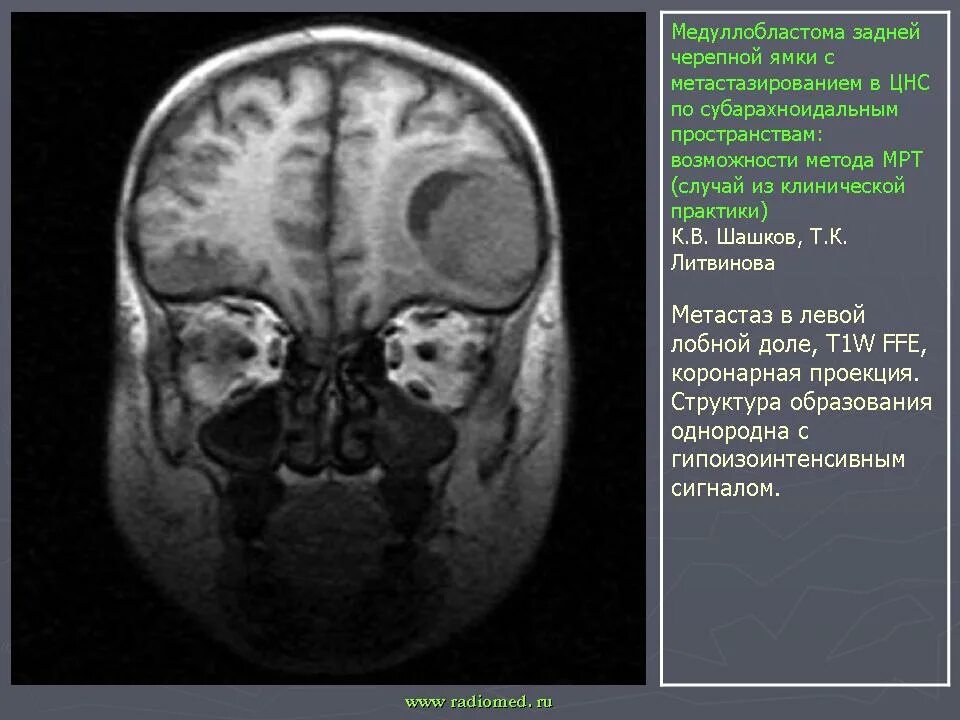

Медуллобластома это